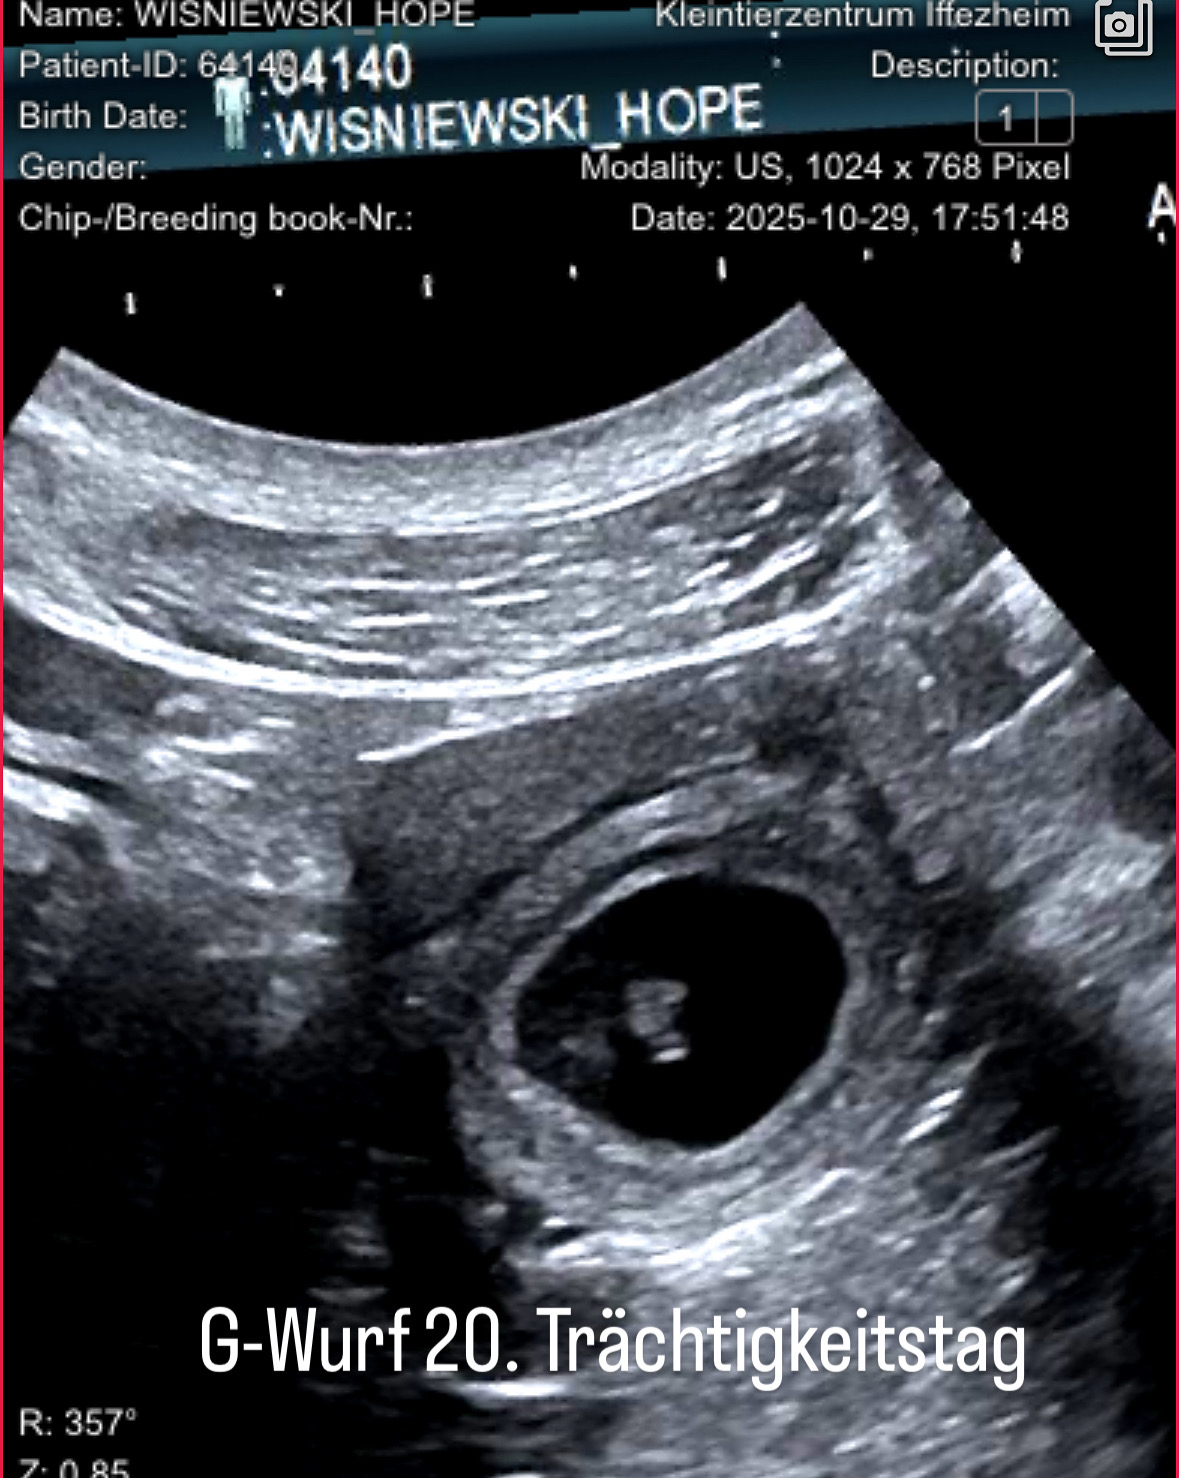

"Hope" ist tragend!

Die heutige Ultraschalluntersuchung zeigt einige vitale Fruchtanlagen. Jetzt heißt es, weiter Daumen Drücken. C79DBE79-E01A-4182-A3F3-E636A47D5DB2